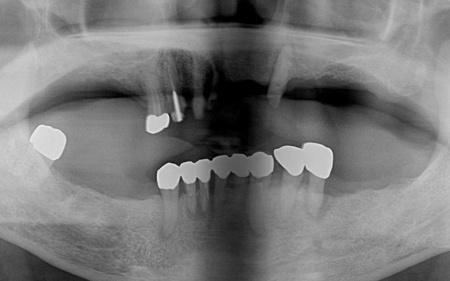

拝見したところ、すでに複数の歯が欠損しており、上下顎には入れ歯が装着されていました。

残っている歯についても、長期間の負担により状態が悪く温存が困難な歯や、細菌感染した神経を取り除いてから薬を詰める根管治療が必要な歯がありました。

まずは、歯根を支える骨が溶けてなくなる歯周病が進行しており、長期的な維持が難しいと判断した左下奥歯(第2小臼歯)を丁寧に抜きます。

次に、上下左右の奥歯部に1本ずつ、左上前歯に1本、計5本のインプラントを埋入する手術を行いました。

続いて、残存している上の歯に対しては根管治療を行いました。

ただ、右上前歯(犬歯)は状態が十分に改善せず、温存が困難であると判断したため、抜歯を行いました。